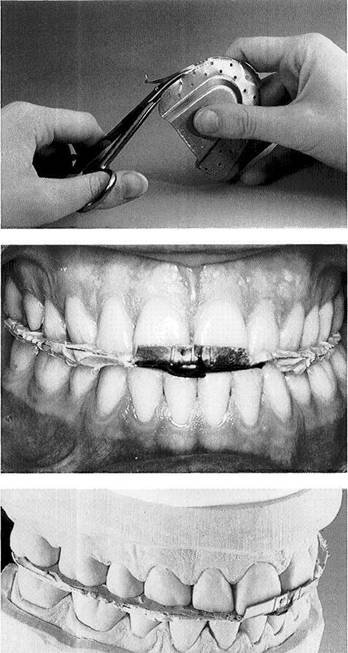

Left: The pretreatment on this pa­tient has been completed with the help of a canine-guided equilibra­tion splint. The patient is free of her previous complaints, and maximal intercuspation with the splint has been stable for 4 weeks.

Right: The occlusal contacts have been marked on the splint with black articulating film.

Application of registration paste

Left: Testing the eccentric occlu­sion. The excursive paths marked with red articulating film extend equally. No excursive interferences can be detected in the posterior re­gions.

Right: A fine-detail registration paste is applied to the splint only over the first premolars and distal-most mo­lars.

Registration of the maximum intercuspation position on the splint

Left: With the head in the upright position, the patient closed gently against the splint. After the regis­tration paste has hardened, the previously marked centric contacts should always be visible at the depths of the occlusal imprints.

Right: In preparation for mounting the mandibular cast, the "splint registration" is seated on a dupli­cate maxillary cast made before the splint was constructed.